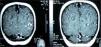

En el estudio realizado en el segundo ingreso se constata la similitud de las imágenes radiológicas torácicas entre la primera y la segunda estancia hospitalaria (fig. 1), lo cual, unido al episodio neurológico transitorio recogido en la anamnesis, hizo sospechar la posibilidad de que se tratara del mismo proceso infectivo tuberculoso y que el antecedente de hemiparesia se debiera a una participación cerebral del mismo. Por ello, se solicitó la realización de una resonancia magnética cerebral, en la que se puso de manifiesto la presencia de múltiples lesiones diseminadas de hiperseñal en secuencias T2 y FLAIR. Se observan captaciones nodulares intensas de gadolinio en la región hemibulbar derecha, hemipeduncular izquierda, temporal profunda medial izquierda, región occipital izquierda y región cortical parietal izquierda. Impresión diagnóstica: múltiples lesiones diseminadas de hiperseñal en la región infratentorial y supratentorial, lo cual parece sugerir la presencia de tuberculomas activos (fig. 2). Tras solicitar el consentimiento informado, se realizó punción lumbar, con los siguientes resultados: glucosa 47mg/dl, proteínas 27mg/dl, leucocitos 30/μl (polinucleares 10 % y mononucleares 90 %). Cultivo de bacilo de Koch en el líquido cefalorraquídeo negativo. En el estudio oftalmológico se encontró un pequeño foco en la retina bien delimitado compatible con tuberculoma coroideo. La serología VIH fue negativa.